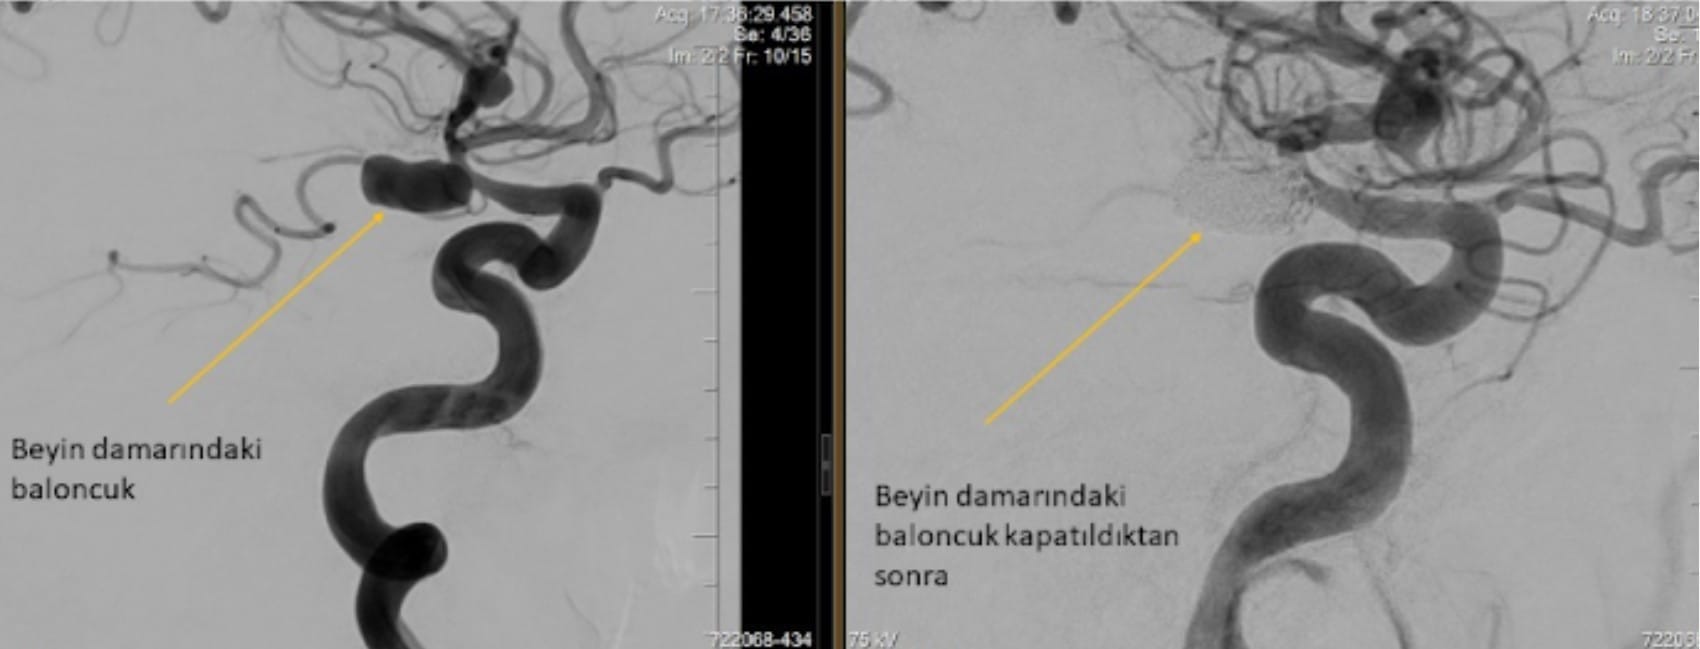

- beyin anevrizma tedavisi öncesi sonrası görüntüsü

Beyin anevrizması, damar duvarlarının zayıflaması ile oluşur ve tedavisi hayati önem taşır. Girişimsel nöroradyoloji alanında uygulanan endovasküler tedavi, bu sağlık sorununa müdahalede önemli bir yöntemdir. Hastalar genel anestezi altında, ameliyatsız bir prosedürle tedavi edilir. İşlem, anjiyografi ünitesinde gerçekleştirilir ve cerrahi kesilere gerek duyulmaz.